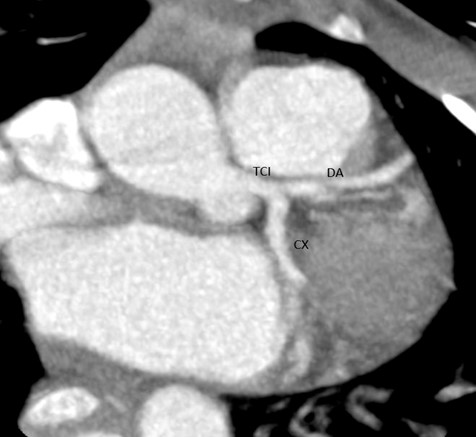

La angiotomografía coronaria demostró un origen anómalo de la arteria coronaria derecha a partir del seno coronario izquierdo, con trayecto interarterial entre la aorta y el tronco de la arteria pulmonar, asociado a una reducción aproximada del 50% del calibre en su segmento proximal (Fig. 1). Adicionalmente se observó leve dilatación difusa del tronco coronario izquierdo y del segmento proximal de la arteria circunfleja, sin evidencia de aneurismas ni estenosis en los segmentos medio y distal (Figs. 2 y 3).

Figura 3. Se evidencia arteria circunfleja de origen y trayecto habitual, segmento proximal con ligera dilatación difusa, primer ramo obtuso sin lesiones, segmento distal sin lesiones. Arteria descendente anterior con origen y trayecto habitual, sin evidencia de enfermedad ateroesclerótica, zonas de estenosis o dilataciones en sus tres segmentos, primer y segundo ramo diagonal sin lesiones, primer ramo septal sin lesiones. CX: arteria circunfleja, DA: arteria descendente anterior.